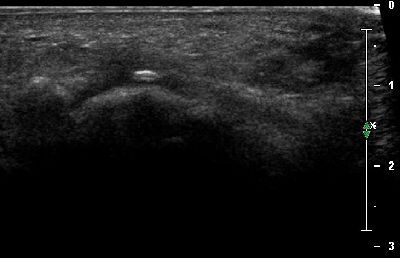

Ipoplasia dei sesamoidi del primo dito (img. 01) Ipoplasia dei sesamoidi del primo dito (img. 01)

Ipoplasia dei sesamoidi del primo dito (img. 02) Ipoplasia dei sesamoidi del primo dito (img. 02)